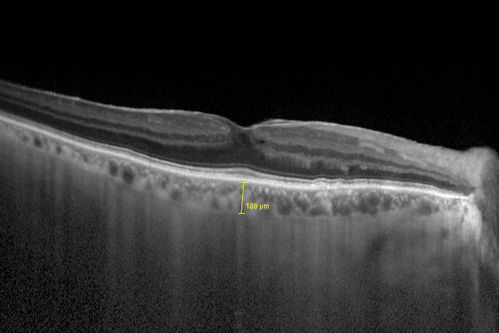

Choroidal Hemangioma - Diffuse - Enhanced Depth Imaging Spectral Domain OCT Line Scan - Normal Eye

Normal Choroidal Thickness in Right Eye